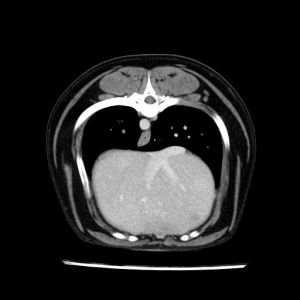

La lesione focale epatica , la ceus,la Tac e il chirurgo .